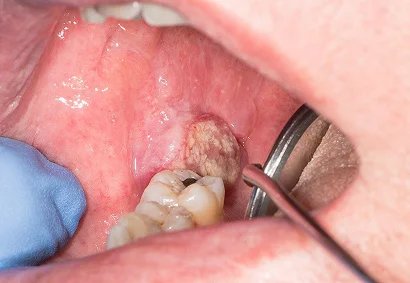

At Faith Hospital, we are dedicated to providing comprehensive, advanced, and compassionate cancer care under one roof. Dr. Zuber Vaja, specializes in Oral and Head & Neck Cancer Surgery, offering personalized treatment plans tailored to each patient’s unique needs. With expert care and modern technology, we focus on healing that restores both health and confidence.

Dr. Zuber Vaja

Head & Neck Cancer Surgeon